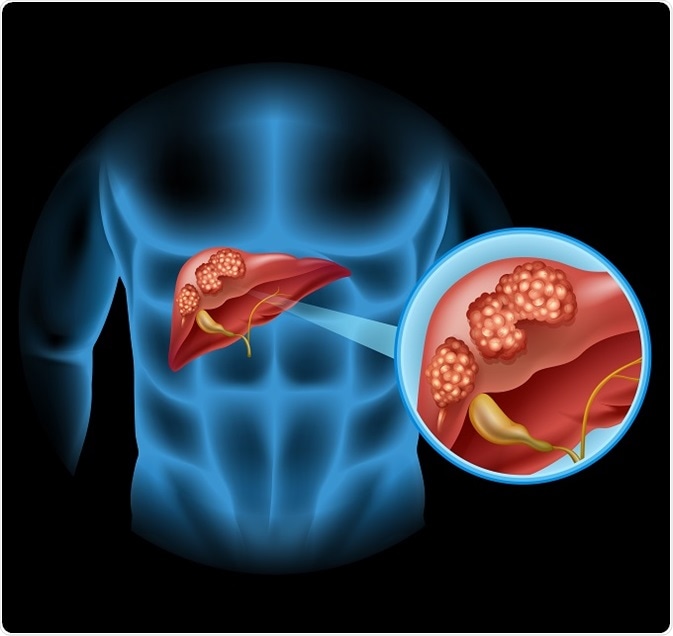

Bile Bile ducts are thin tubes that connect the liver with the small intestine. These ducts transport bile (digestive fluid) formed in the liver and the gallbladder.

The bile duct system consists of a series of ductules (small tubes) in the liver that combines into ducts called the intrahepatic bile ducts. The duct coming from the gallbladder is called the cystic duct. The cystic and intrahepaticducts merge to form the common bile duct, which joins with the pancreatic duct and then reaches into the duodenum (beginning of the small intestine).

Cancer in any part of these bile ducts is termed as cholangiocarcinoma. Adults aged above 65, usually males, and those having colitis or other forms of liver disease are at increased risk of having cholangiocarcinoma. The tumors involved in bile duct cancer metastases via the lymphatic system and then into the blood vessels that go into the liver.